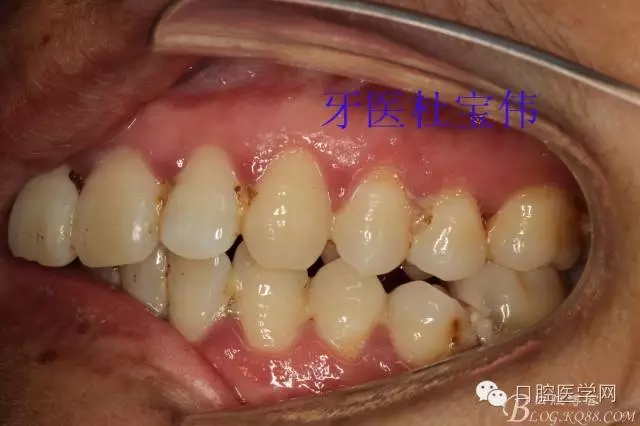

患者都是以刷牙出血為主訴。術(shù)前照片

術(shù)后照片